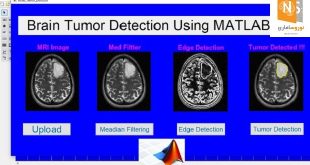

نوروسافاری | محققان از بخش روانشناسی تجربی، مرکز تصویر برداری عصبی یکپارچه وِلکام (WIN) و بخش علوم اعصاب بالینی نوفیلد (وابسته به دانشگاه آکسفورد)، برای رصد تغییرات اتفاق افتاده در مناطق مغزی مرتبط با یادگیری و تجارب آموخته شده از پیمایشگر MRI استفاده کردند در حالی که داوطلبان مشغول تکمیل تکالیفی بودند که پاداشی در پی داشت. همچنین داوطلبان پیش از اسکن، به منظور مقایسه ی تداعی های شخصی شان بین توالی های محرک و پاداش، در دو جلسه ی مقدماتی حضور یافتند.